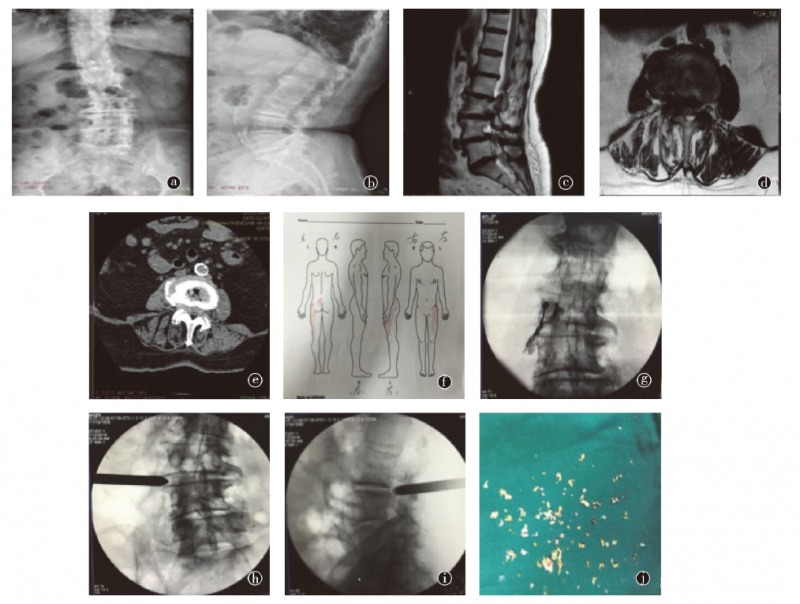

图3 患者女性,85岁,因左下肢疼痛伴间歇性跛行6个月就诊,查体:左侧大腿前外侧痛觉略减退,余(-)。a、b.术前正侧位X线片;c.腰椎MRI矢状位T2像;d.L3~4MRI横断面扫描;e.L3~4 CT横断面扫描(软组织窗);f.术前患者的疼痛图谱;g.术前左侧L3神经根封闭;h、i.侧路全内镜下L3神经根减压;j.术中取出的椎间盘及韧带组织

从患者的诊疗过程中可以发现,术前的节段定位十分重要,那么是否可以仅从术前的影像学,如MRI的结果来判定椎管狭窄患者的手术节段?有学者回顾性分析了1839例腰椎椎管狭窄的患者,共有2076个腰椎节段进行内镜下手术治疗,平均随访33个月,术后应用MacNab标准和VAS评分来判断术前应用MRI分级是否可以判定内镜下手术的效果。结果显示共有1750例患者术中可见腰椎椎管外侧区狭窄,而89例患者无狭窄。同时,放射科医师与微创脊柱外科医师对MRI结果的解读是有区别的。所以,外科医师要在术前仔细、独立地判断MRI所示病变的位置。同样,对于应用脊柱内镜治疗腰椎椎管外侧区狭窄再手术(再入院)的情况,作者也进行了回顾性分析,在1839例患者中,仅有29例(占3. 3%)患者出现了疼痛缓解不明显的情况,所以,作者认为应用脊柱内镜治疗腰椎椎管外侧区狭窄时再手术的情况不多见。